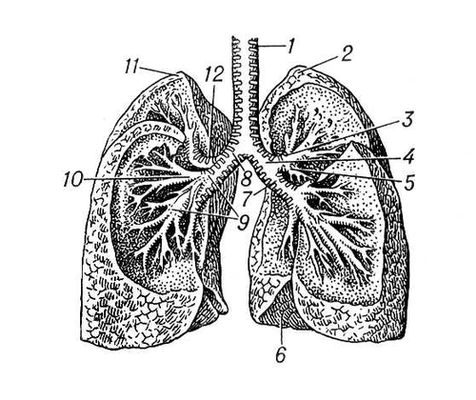

Анатомические изображения сегментов легких различных животных

Раздел: Другие животные